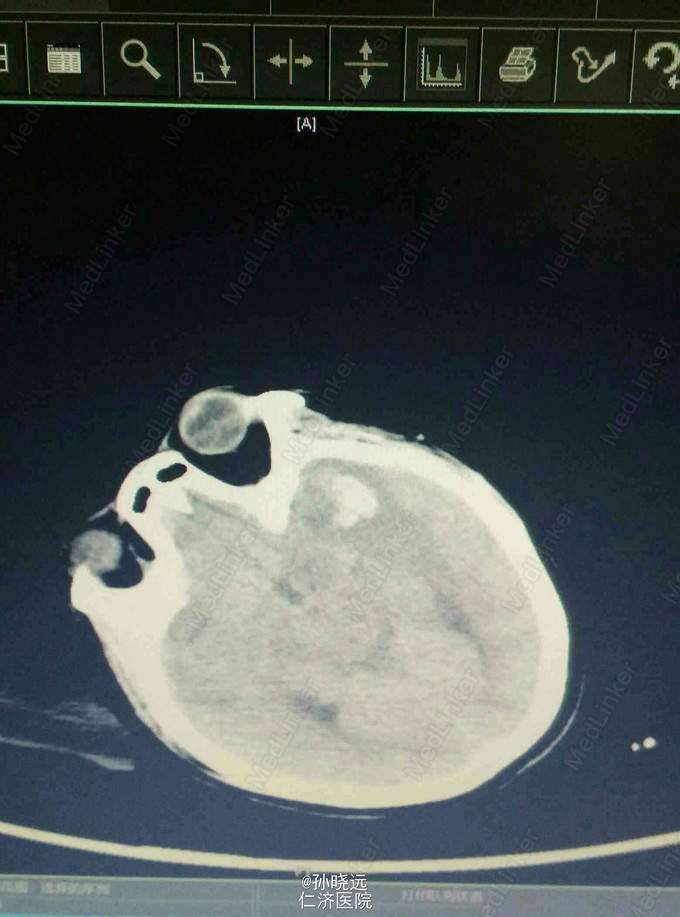

中年女性。主诉:头晕三天,发热伴神志不清1天。 患者于三天前出现持续性头晕,无恶心、呕吐,无视物旋转,来院就诊,查头颅MRI未见异常,予桂哌齐特、长春西汀、硫辛酸治疗,症状无好转。1天前出现高热,最高39.5℃,无咳嗽、气促,再次来院就诊,查血常规:WBC:5.85*10^9/L,N:71.8%,CRP正常,予退热,阿奇霉素等治疗,今日凌晨出现神志不清,无抽搐、恶心、呕吐,头颅CT示两侧颞底部不规则斑点样密度增高影并周围低密度灶,考虑脑炎合并灶性出血,予更昔洛韦、醒脑静、喜炎平、奥美拉唑、甘露醇治疗。后出现氧饱和度下降,予气管插管有创呼吸机辅助通气。 既往史:曾有高血压病史,未应用降压药。

诊断:脑炎。脑出血。 治疗:甲强龙抗炎,更昔洛韦,青霉素钠抗感染,降压,甘露醇、甘油果糖、白蛋白、拖拉塞米里降颅压,呼吸机辅助通气等对症治疗。

腰穿是: 脑脊液生化:葡萄糖:12.18mmol/L,CL:110.9mmol/L,蛋白:222.4mg/dl, 脑脊液常规:淡黄,微混。红细胞:1000*10^6/L,白细胞:1059*10^6/L,潘氏试验阳性(++++),嗜中性粒细胞12%,淋巴细胞:80%,单核细胞8%,凝块无,细菌未找到。 予加用血必净,加强抗感染等治疗。 患者目前仍昏迷,正进行高压氧仓治疗。这是最近一次复查的头颅CT。